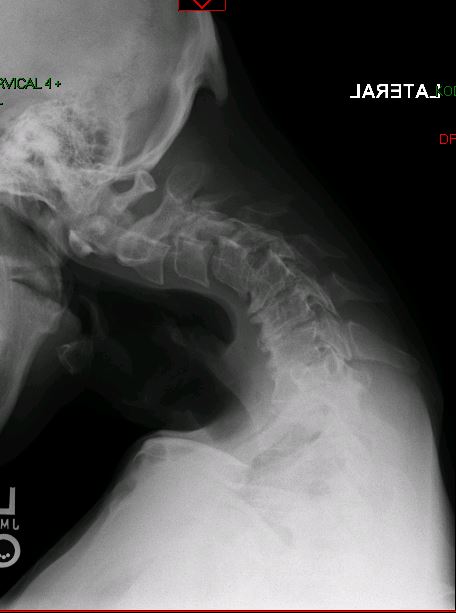

De-identified imaging from complex spine surgery cases. Each pair shows pre-operative pathology alongside post-operative correction across cervical, lumbar and deformity subspecialties.